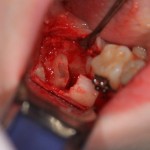

Далее, разрез. Создаем доступ к зубу. Для этого используется повышающий наконечник с соответствующими фрезами. Вот они, восьмерка и семерка:

Чтобы аккуратно удалить восьмерку и не повредить соседний зуб, мы делим ее на две части. НИКАКИХ МОЛОТКОВ И ДОЛОТОВ))) Все делается, исключительно, с помощью фрез: